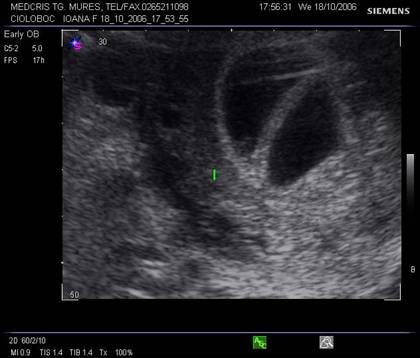

Fig nr 36 Sarcina gemelara biamniotica, 6 sapt, cu 2

saci amniotici si 2 embrioni (cu sageata )

Fig nr 37. Aceeasi sarcina gemelara de 6 sapt., sectiune fara embrioni,cu sacii amniotici caracteristic dispusi in ochi de bufnita